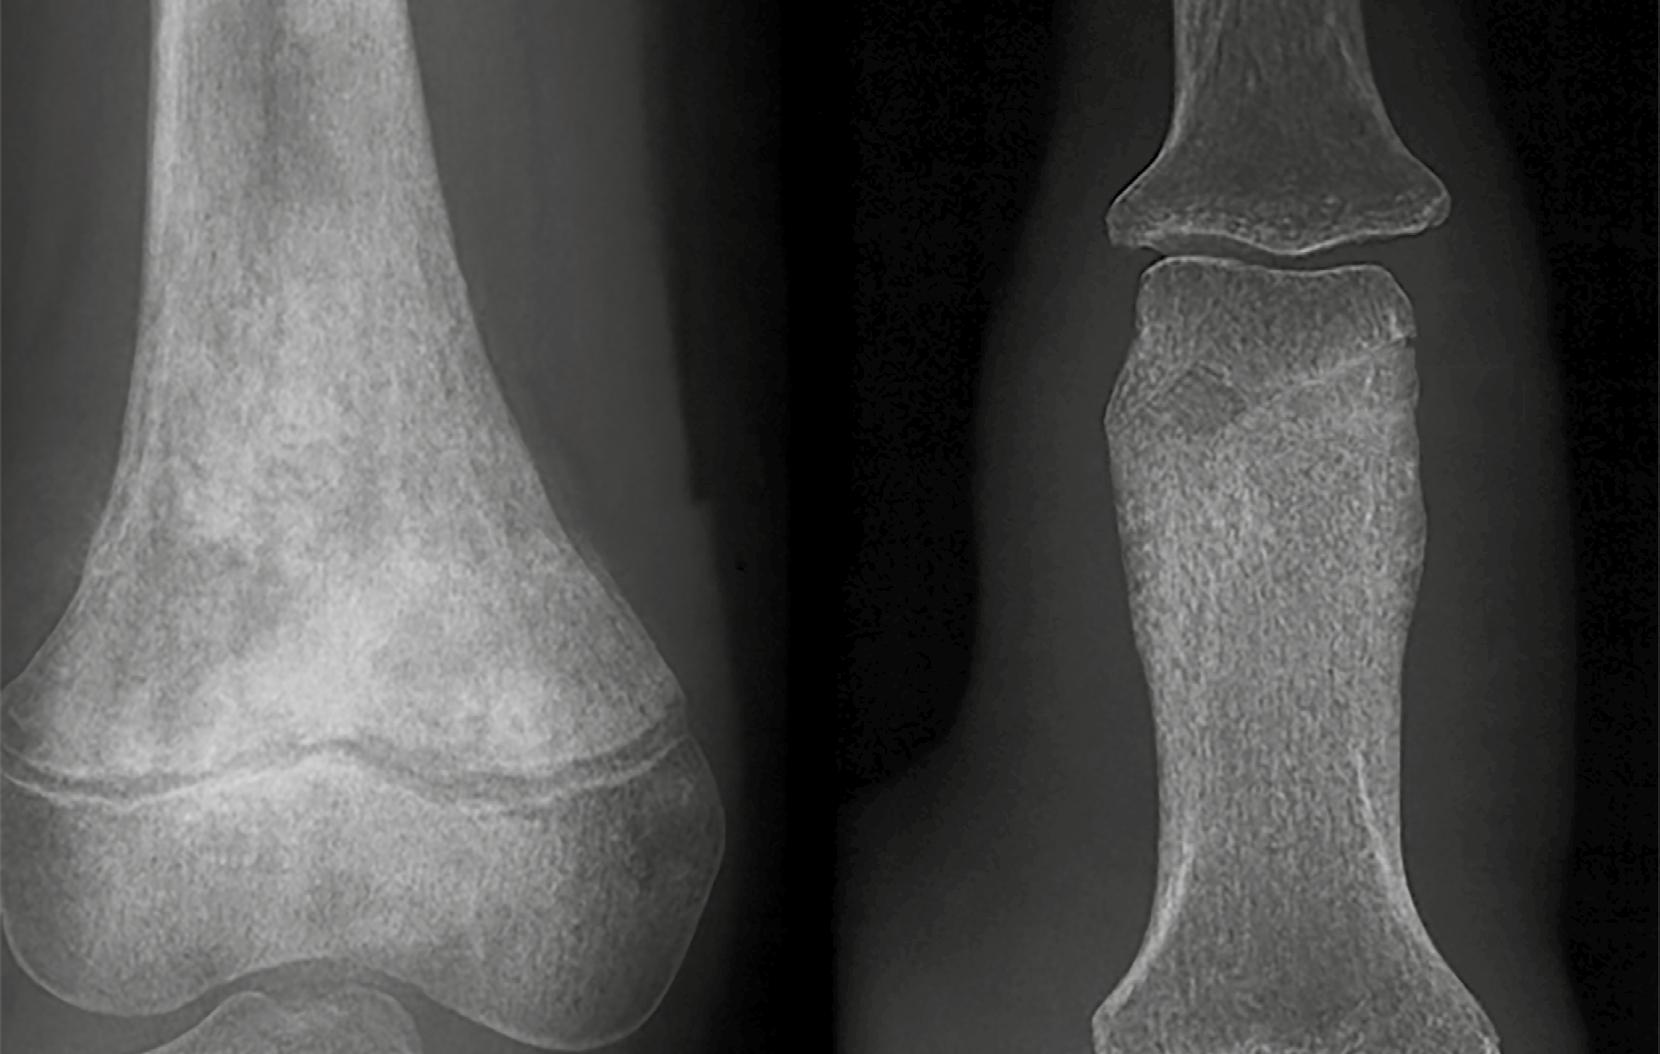

Un patrón particular de afectación cortical es el abombamiento, donde la destrucción del hueso endóstico y la formación de hueso nuevo en la superficie externa se dan al mismo ritmo (Figura 8). Este proceso produce una expansión del hueso con una corteza nueva, neocórtex, que puede lucir lisa y continua. No

Romel Segura-Galvis

obstante, en lesiones más agresivas, como el tumor de células gigantes (TCG), esta nueva capa puede mostrar interrupciones focales. El abombamiento es típico de lesiones que crecen lentamente, pero con suficiente fuerza como para remodelar la arquitectura ósea.

Figura 8. El abombamiento. 1. Fibroma condromixoide: una lesión benigna, bien definida y expansiva con destrucción regular del hueso cortical y una capa periférica de hueso nuevo (flecha roja). 2. Tumor de células gigantes: Una lesión localmente agresiva con destrucción cortical, expansión y una capa periférica delgada e interrumpida de hueso nuevo; observar la amplia zona de transición hacia la cavidad medular, lo cual indica un comportamiento agresivo (flecha amarilla). Adaptada de: Jan van der Woude R, Smithuis R. Bone tumors. Differential diagnosis [Internet]. 2010 [consultado 2025 oct 13]. Disponible en: https://radiologyassistant.nl/ musculoskeletal/bone-tumors/differential-diagnosis